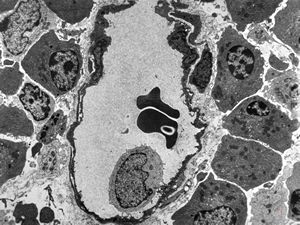

jejunumblood capillarz in lamina propria